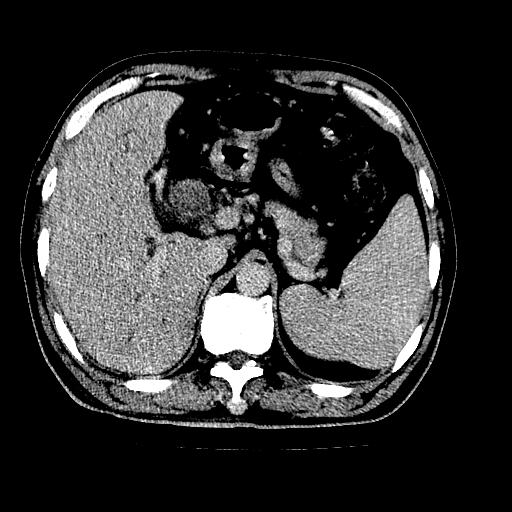

男,66岁,上腹部不适、黄染一周。彩超示:肝左叶占位,肝内胆管扩张,胆总管扩张,胆总管占位?

肝左叶不规则软组织肿块影,边缘不规整邻近肝实质受累分界不清;肝内胆管(左叶)明显扩张成“软藤状”,诊断:肝左叶胆管细胞癌。

肝左叶占位性病变,并胆管扩张,符合胆管细胞癌ct表现,门脉左支受累,左肾囊肿。窗宽太窄了,其他的看不清

左叶胆管细胞癌累及胆总管,门脉左支受侵,慢性胆囊炎胆结石,左肾小囊肿